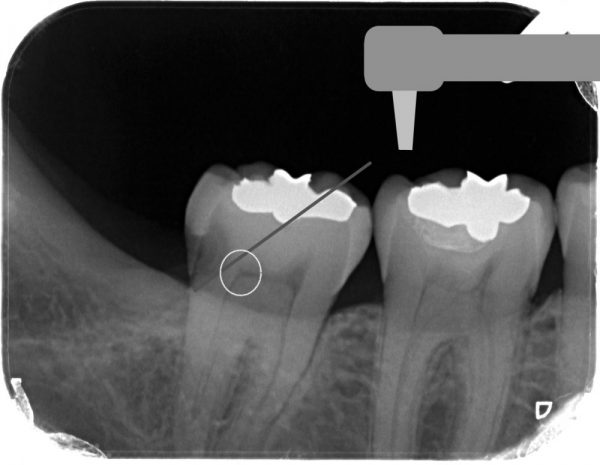

このようにアプローチすることで、健康な歯と神経を残して、かつ虫歯だけを削ることができます。

その後、歯に直接接着する高分子の樹脂(コンポジットレジン)で詰めていきます。

これが詰めた写真です。

神経も残っていますし、虫歯だけをとって歯がたくさん残っています。

3年ほど経過していますが、全く問題ありません。